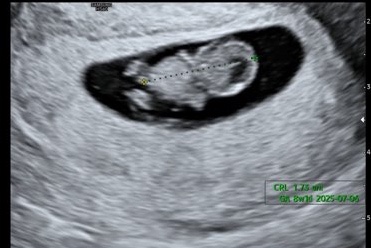

[베이비] 임신 11주차, 여전히 입덧 그리고 먹덧의 시작

12/14 임신 11주차의 시작이다. 드디어 3등신이 된 귀여운 보리? 아침엔 든든하게 토스트와 바나나주스....